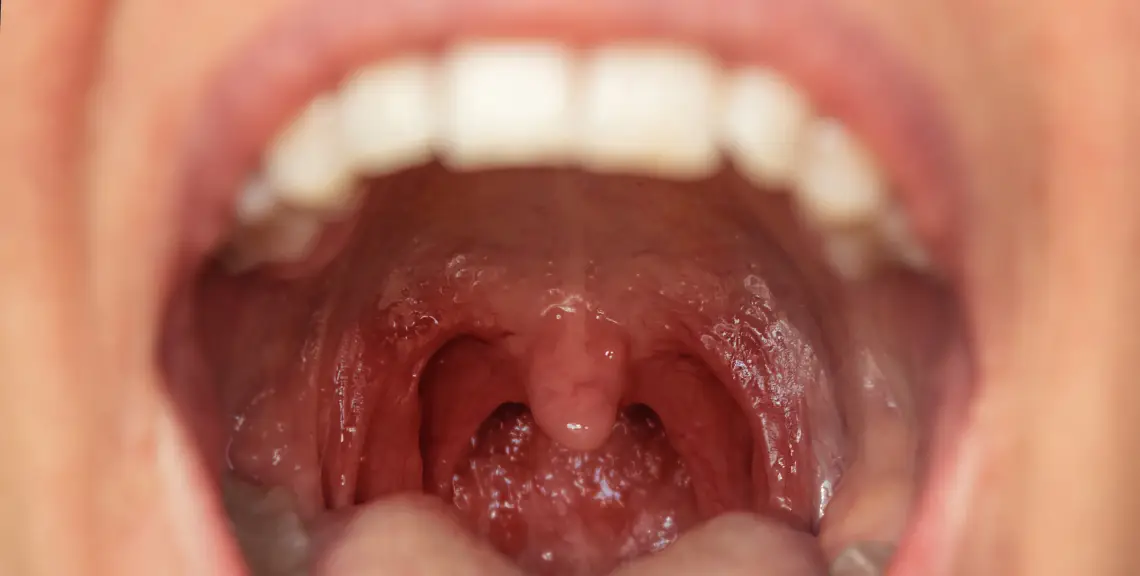

Investigación cáncer oral finlandia

Identificación precoz de cánceres orales con alto riesgo de recurrencia